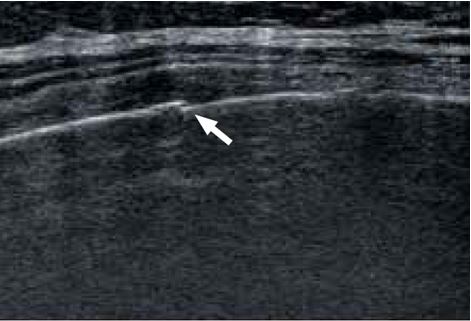

57-річна пацієнтка звернулася зі скаргами на біль у правому верхньому підребер'ї. Проте, незважаючи на численні обстеження, причину болю не було встановлено. При використанні датчика 7 МГц (PLT-704SBT, Aplio 500) (мал. 2а) структура ребер виглядала нормальною. Однак датчик надвисокої частоти виявив невеликий перелом ребра (рис. 2б), який потім був ідентифікований як причина болю. Ці невеликі переломи не могли бути діагностовані іншими методами візуалізації, що підкреслює чіткість і деталізацію, які забезпечує PLI-2004BX.

a) PLT-704SBT (Aplio 500)

б) PLI-2004BX (Aplio i-серії)

Малюнок 2. Зображення перелому ребер, отримані за допомогою PLT-704SBT (7 МГц) (а) та PLI-2004BX (24 МГц) (б).